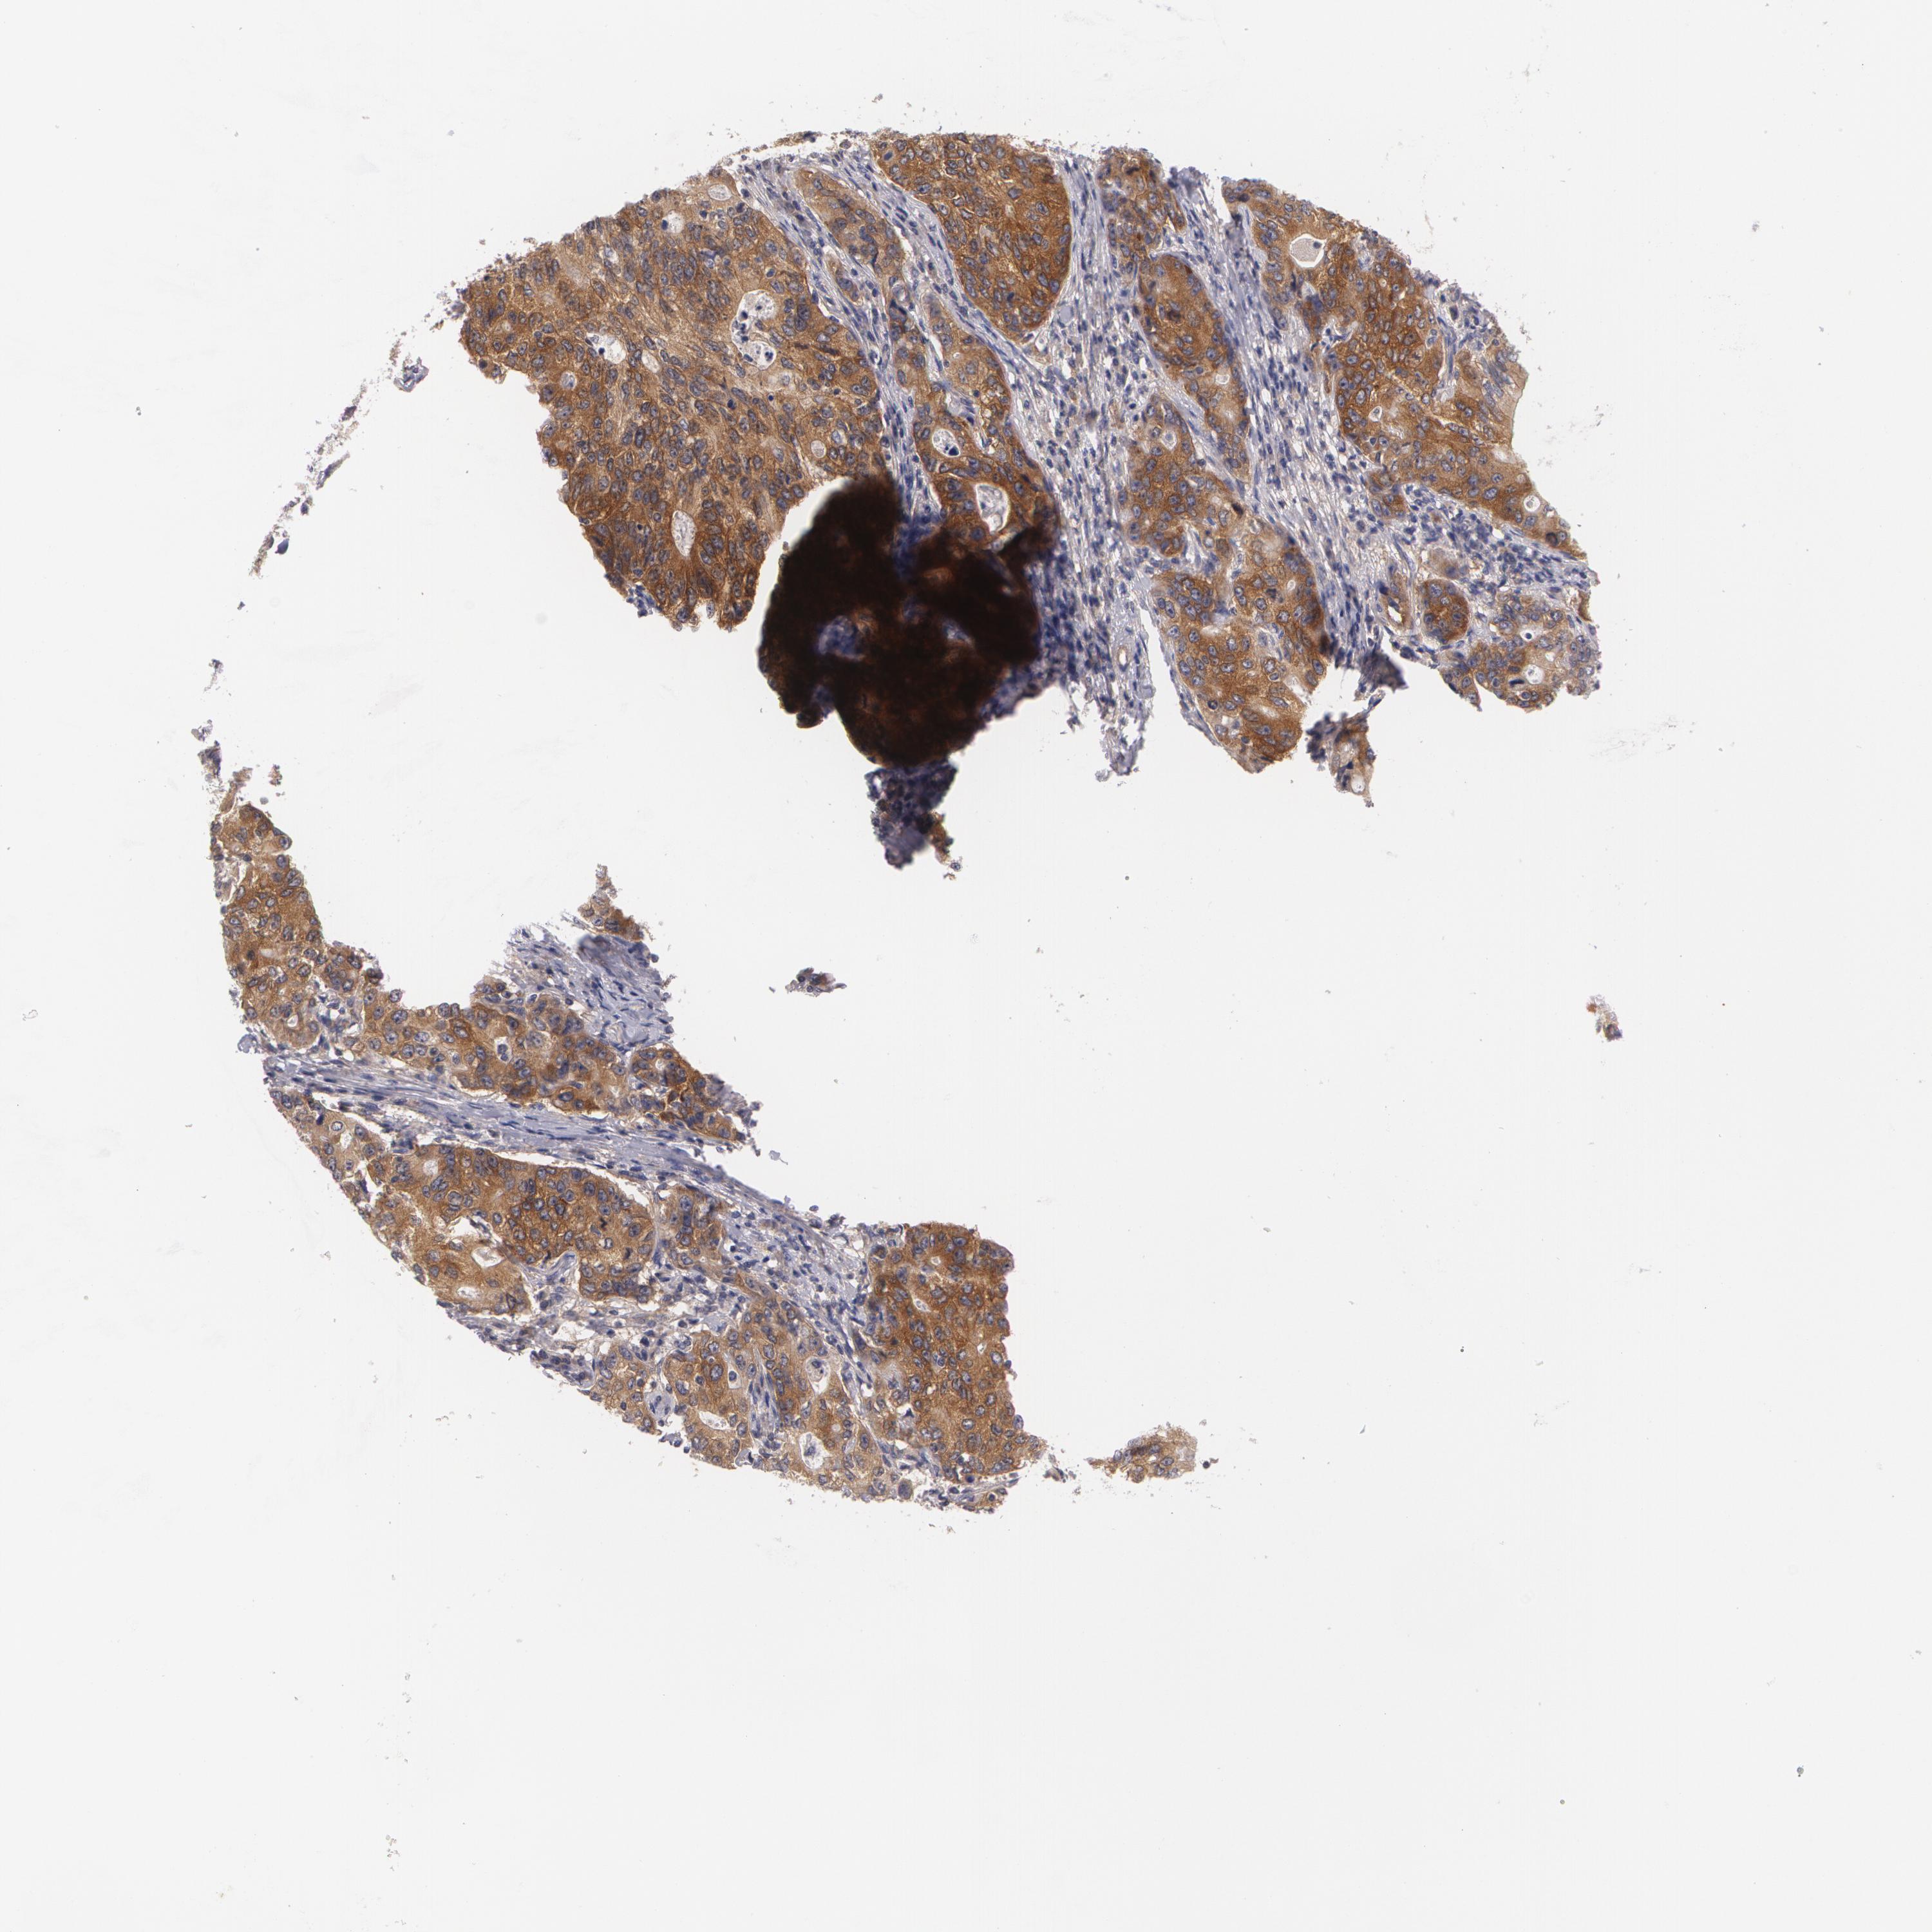

STOMACH CANCER - Protein expressioni

A mouse-over function shows sample information and annotation data. Click on an image to view it in a full screen mode. Samples can be filtered based on level of antibody staining by selecting one or several of the following categories: high, medium, low and not detected. The assay and annotation is described here.

Note that samples used for immunohistochemistry by the Human Protein Atlas do not correspond to samples in the TCGA dataset.

Antibody stainingi

Antibody staining in the annotated cell types in the current human tissue is reported as not detected, low, medium, or high, based on conventional immunohistochemistry profiling in selected tissues. This score is based on the combination of the staining intensity and fraction of stained cells.

Each image is clickable and will lead to virtual microscopy that enables deeper exploration of all samples and also displays staining intensity scores, fraction scores and subcellular localization as well as patient and tissue information for each sample.

Antibody HPA023857

Antibody CAB001949

Staining

High

Medium

Low

Not detected

Intensity

Strong

Moderate

Weak

Negative

Quantity

>75%

75%-25%

<25%

None

Location

Nuclear

Cytoplasmic/membranous

Cytoplasmic/membranous,nuclear

Adenocarcinoma, NOS